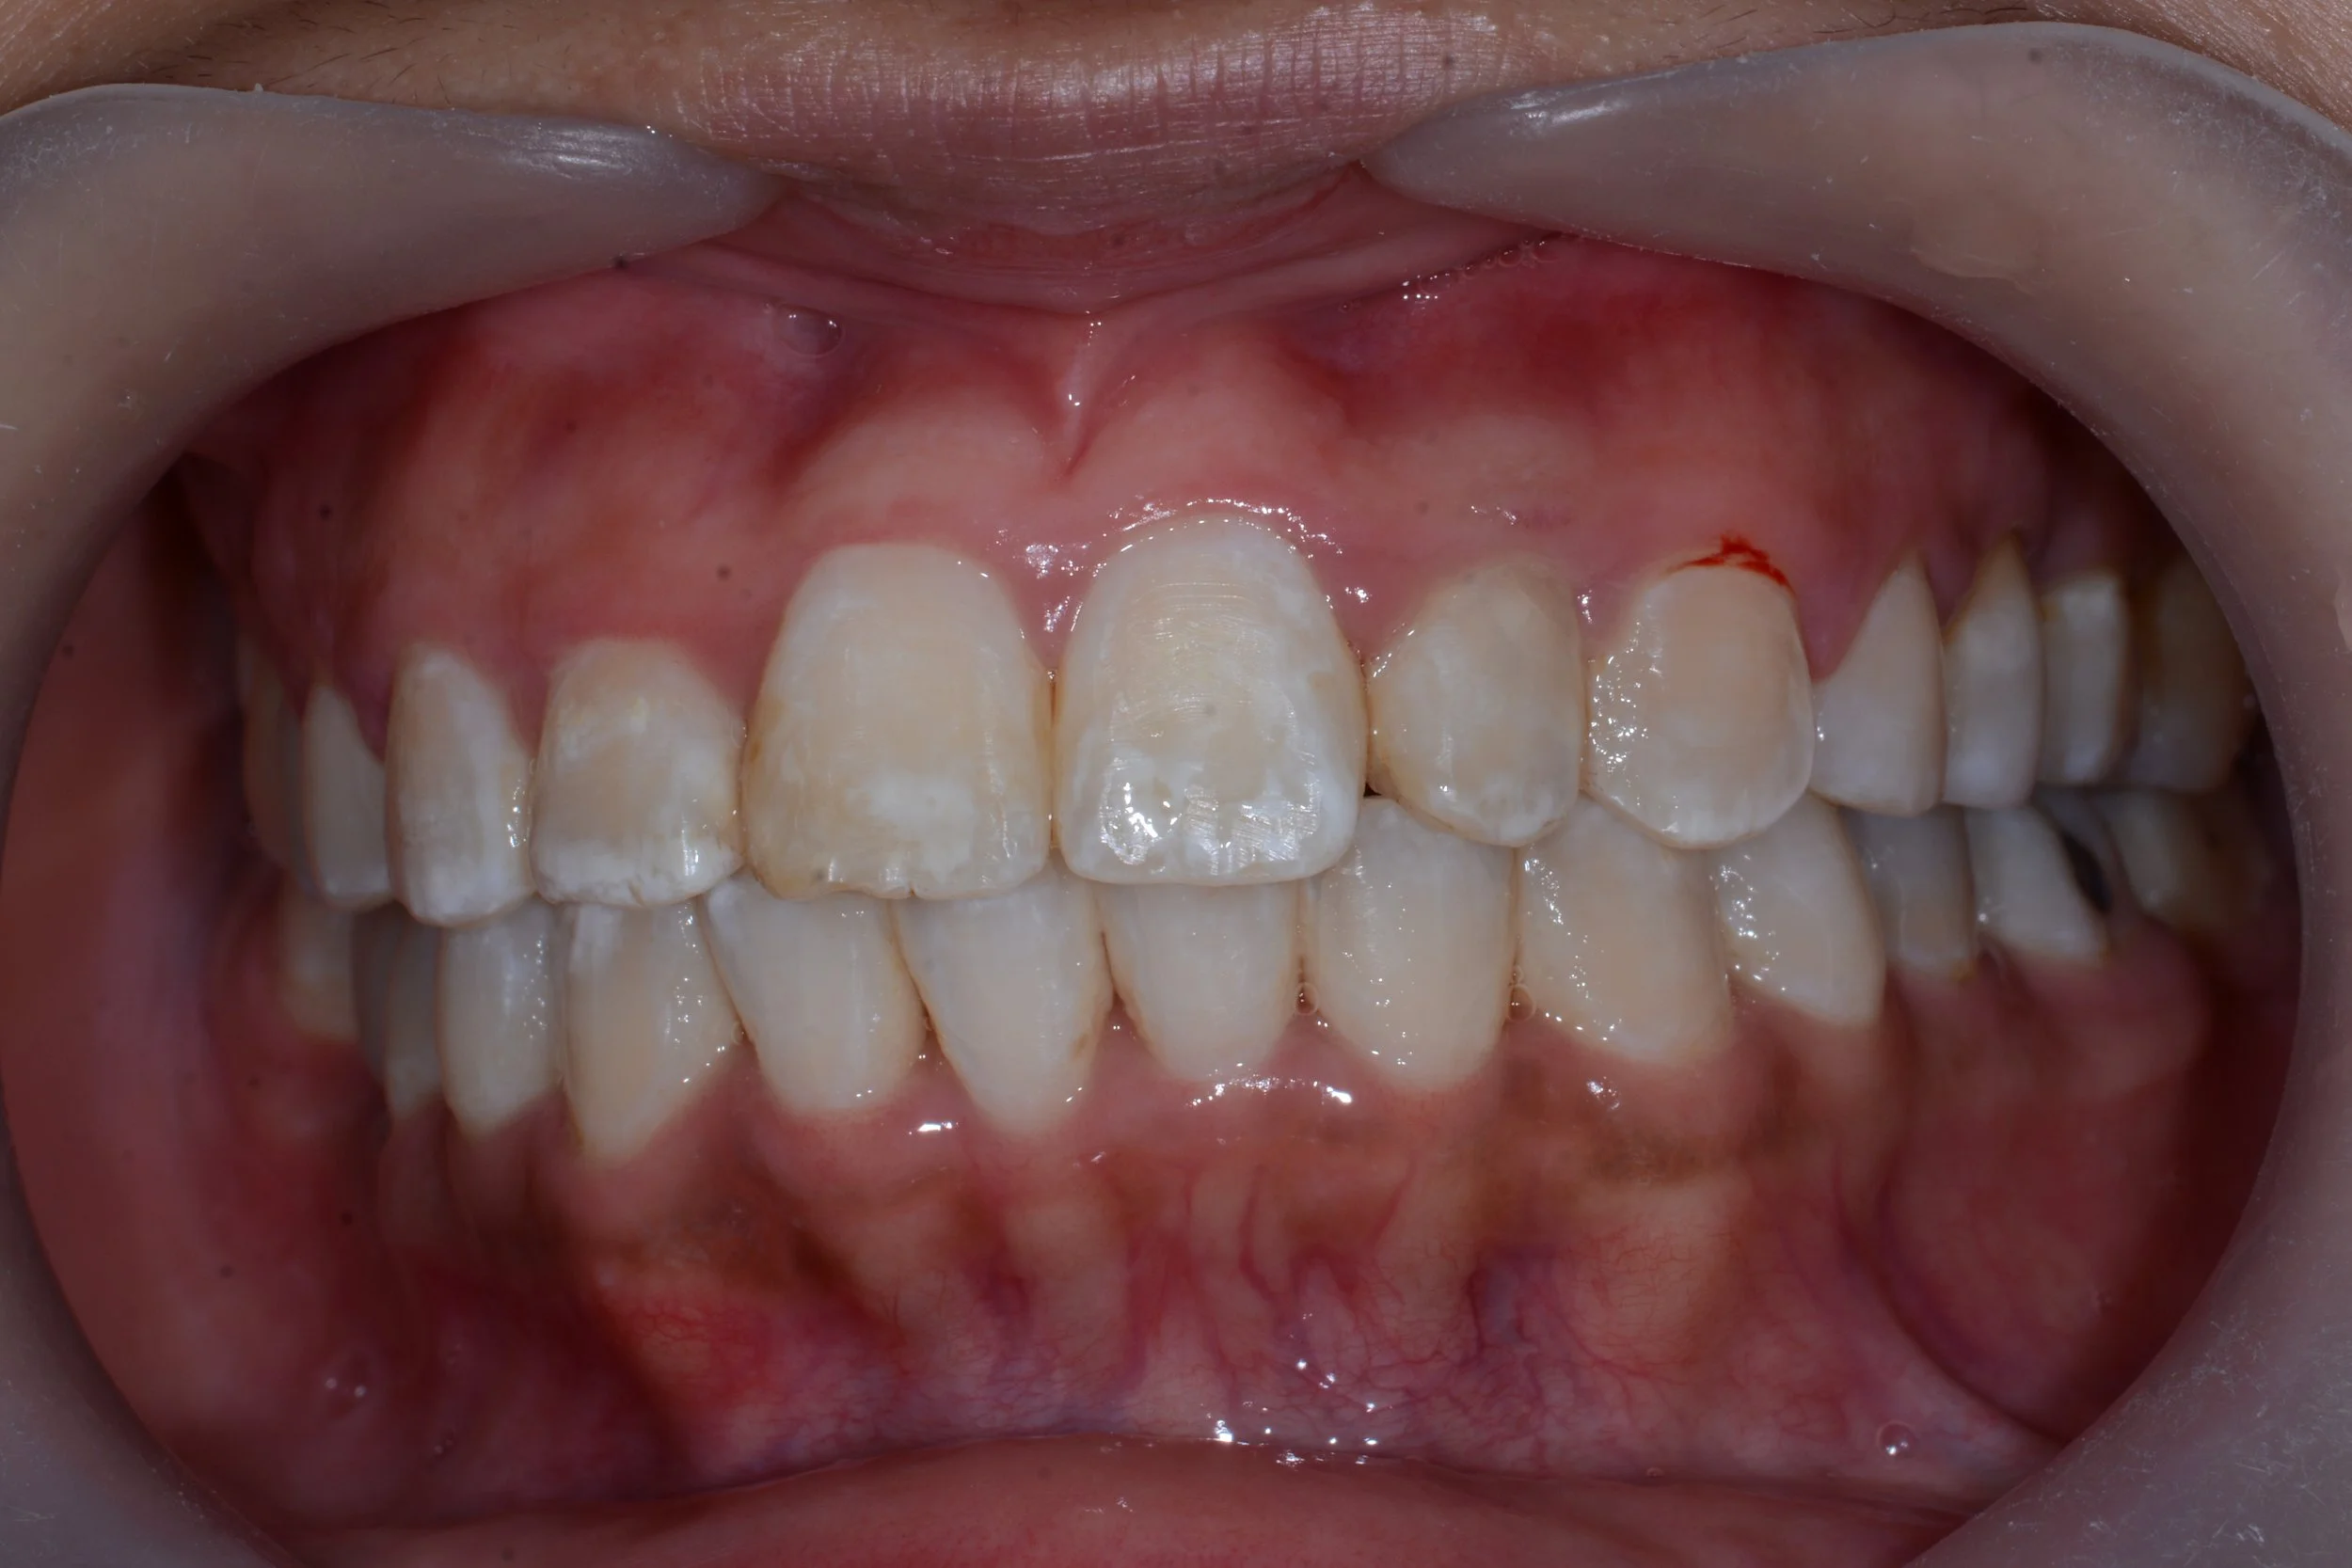

DSC_0285.JPG

AFTER

MULTIPLE TEETH REPLACEMENT

(WITH DENTAL IMPLANTS)